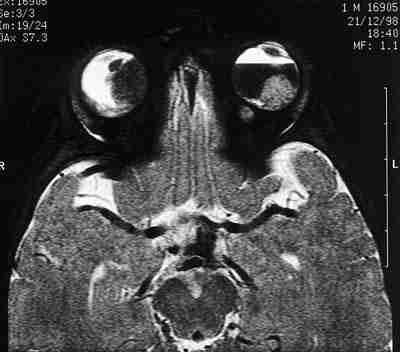

Como ya se comentó anteriormente en este capítulo, la RM es la técnica de elección en el diagnóstico del glioma del nervio óptico para determinar su extensión intracanalicular, quiasmática e intracra neal profunda, sin artefactos en la imagen por estructuras óseas circundantes. La intensidad de señal suele ser similar a la de la sustancia blanca cerebral tanto en secuencias T1 como T2. El realce con gadolínio puede ser moderado o intenso (figura 4).

53-04.jpg (6514 bytes)

Figuras 4a, b y c. Glioma del nervio óptico. Secuencia axial potenciada en T1 tras la administración de Gadolínio (a, b) que muestra el tumor del nervio óptico derecho que no llega al quiasma. Una reconstrucción biplanar (c) logra delimitar mejor la extensión tumoral así como su componente quístico.